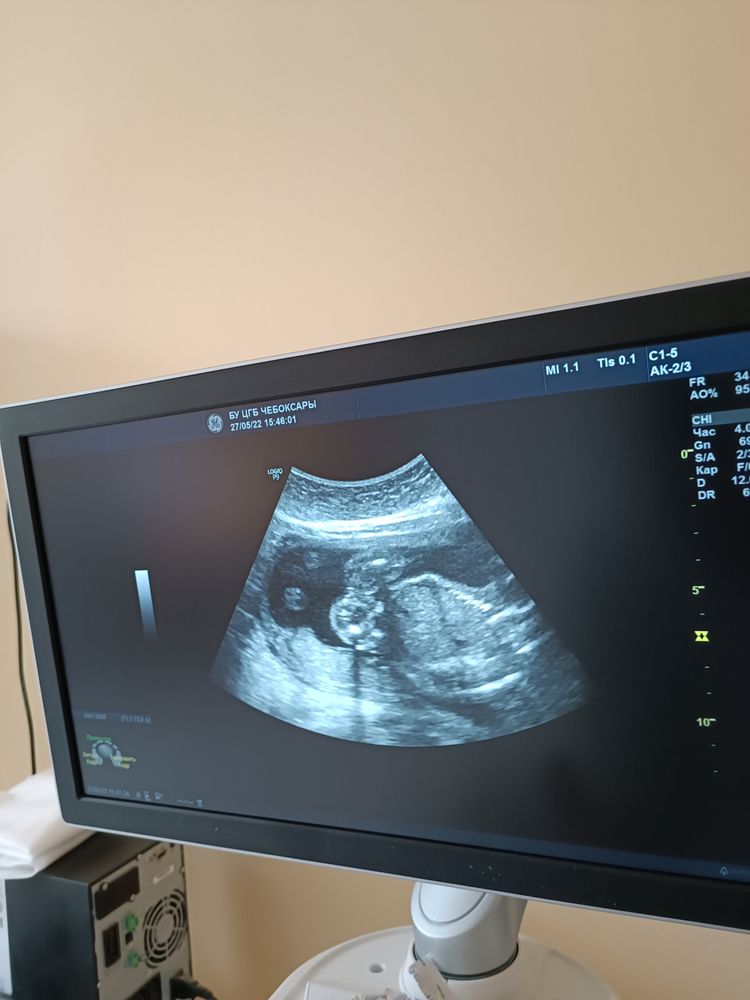

22-ое и 27-ое мая 2022-го года - дни, которые запомнятся мне навсегда небеспричинно: 22-го мая - второй скрининг (в частной клинике) и узистка сообщает, что, скорее всего, будет девочка. Как же я тогда ревела от счастья и никак не могла поверить, что мне так повезло! А 27-го мая в ЖК уже подтверждают пол будущего ребенка, и это стопроцентная девочка!